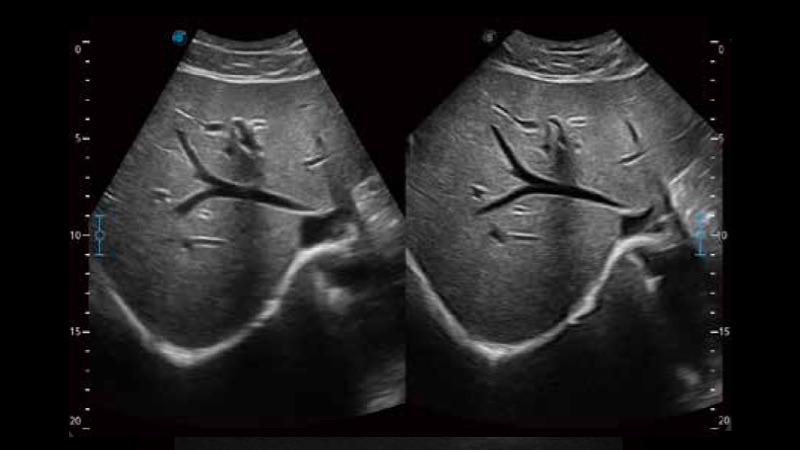

SR Flow高分辨率血流成像

高分辨率血流成像技术提高了对低速血流信号的检测能力。在提高空间分辨率的同时,也克服了血流外溢现象,为用户提供更加真实的血流动力学信息。